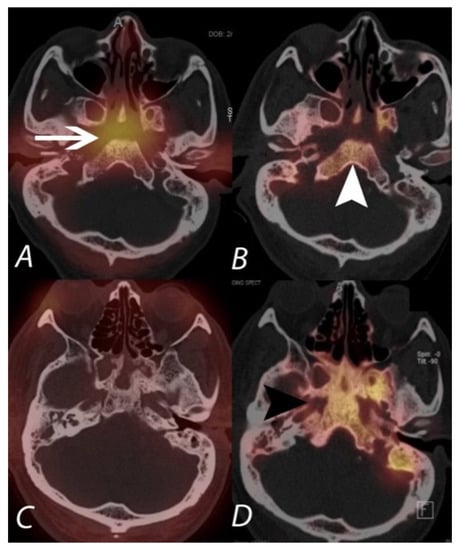

8. SPECT/CT of Extremities

9. Infection and Inflammation